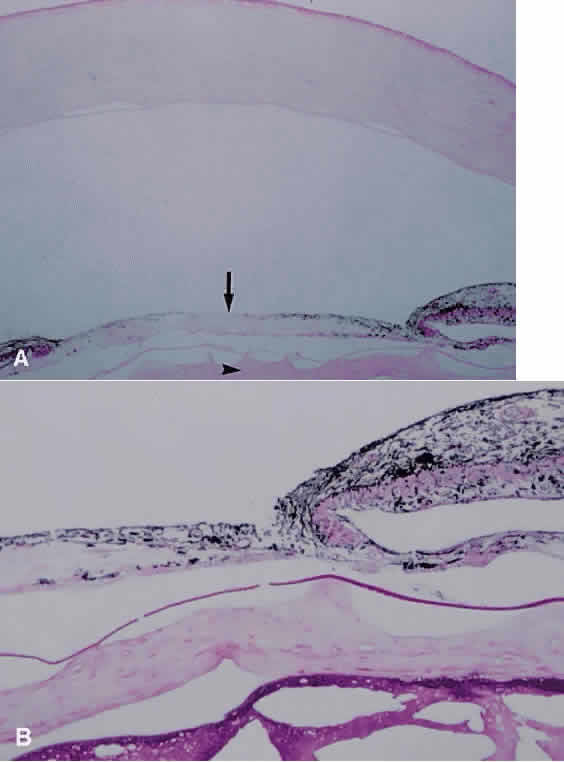

An integral portion of inflammation is the release of fibrin and other inflammatory mediators into the intraocular environment. The presence of these factors in the aqueous humor may result in the formation of adhesions between the iris and underlying lens capsule, termed posterior synechiae (Fig. 20); or iris and peripheral cornea, termed peripheral anterior synechiae. Development of posterior synechiae for 360 degrees of the pupillary margin results in a secluded pupil and prevents the normal flow of aqueous from the posterior chamber to the anterior chamber. Assuming aqueous production continues, the resultant increased pressure in the posterior chamber results in the forward bowing of the mid and peripheral iris, producing iris bombé. Development of iris bombé may result in elevated intraocular pressure as the peripheral iris occludes the trabecular meshwork. If apposition between the peripheral iris and trabecular meshwork continues, then the previously described peripheral anterior synechiae may form, making the angle closure permanent (Fig. 21). This is hastened if active inflammation is present at the time of apposition. Timely creation of an alternate bypass channel for aqueous flow from the posterior to anterior chambers of the eye (before the development of peripheral anterior synechiae) allows equalization of the pressure and resolution of iris bombé. This bypass channel may be created using the argon or neodymium:YAG (Nd:YAG) lasers (and is then called a peripheral iridotomy) or surgically, by removing a piece of peripheral iris through a limbal incision (termed a peripheral iridectomy). With active inflammation, the generally larger opening of the surgical iridectomy may be preferred to decrease the chance of the opening from closing because of fibrosis. If fibrosis continues, then growth of a membrane may occur across the pupillary space as well. When the pupil is covered, it is said to be occluded (Fig. 22). Because of the common mechanism of formation, seclusion and occlusion of the pupil often are seen, at least somewhat, in tandem.

Fig. 21. Photomicrograph of eye enucleated after endophthalmitis. Broad peripheral anterior synechiae are present, as well as a fibrous membrane on the surface of the iris (arrow) (periodic acid-Schiff; × 31).

Fig. 22. A. Photomicrograph showing fibrous membrane stretching across the pupil (arrow). Lens visible at lower portion of figure shows fibrotic anterior subcapsular cataract (arrowhead) (hematoxylin and eosin; × 31). B. Higher magnification highlights the fibrous cataract present beneath the lens capsule (periodic acid-Schiff; × 80).